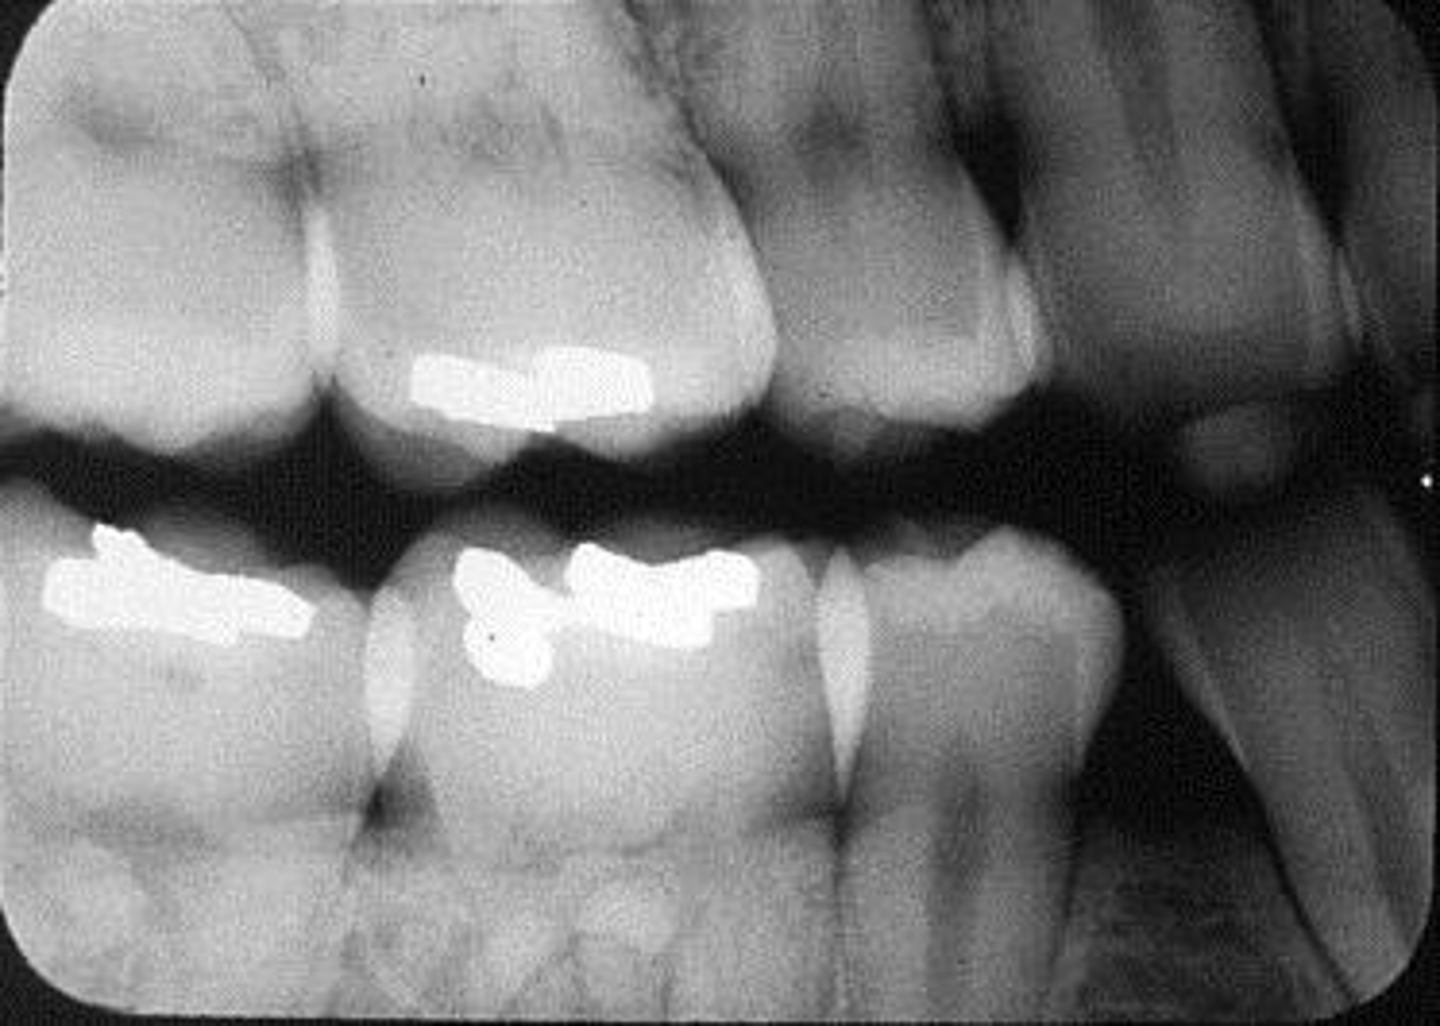

What is this projection of?

Premolars projection